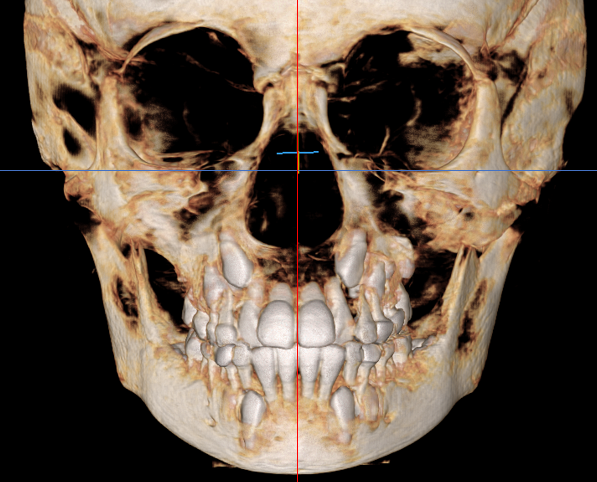

어린이들은 아직 성장이 진행 중이기 때문에, 치열 뿐만 아니라 골격적인 부분에도 다른 문제는 없는지 함께 꼼꼼하게 검진하는 것이 필요합니다.

이렇게 정밀한 검진을 통해 골든타임을 놓치지 않고 제때 필요한 치료를 받을 수 있게 됩니다.

특히 성장판 검사(손목 엑스레이)도 함께 진행하여 현재 아이의 성장 상태를 정확히 파악하는 것이 중요합니다.

이 시기에는 단순히 치아의 위치만 바로잡는 것이 아니라, 턱뼈의 성장 방향과 속도를 적절하게 조절할 수 있습니다.

이러한 골격적 문제를 성장기에 개선하지 못하고 방치할 경우, 성장이 완료된 후에는 교정치료만으로 해결하기 어려워져 외과적 수술이 필요할 수도 있습니다.